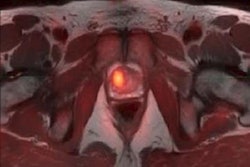

Ga-68 BBN-RGD PET/CT of a 64-year-old man with newly diagnosed prostate cancer shows multiple bone metastases (arrow). Image courtesy of JNM and Jingjing Zhang, Peking Union Medical College in Beijing.The results are better than scanning with a methylene diphosphonate (MDP) radiopharmaceutical, and no adverse side effects were found during the procedure and a two-week follow-up.